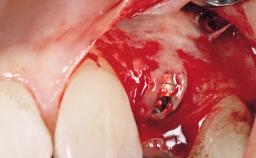

Immediate Placement of an Implant in a Maxillary Right Central Incisor Site

A 30-year-old female patient was referred to the office for the treatment of tooth 11. Her chief concern at the initial visit was to inquire, “Why is my tooth pink?” Upon clinical examination, it was determined that tooth 11 had a previous history of trauma and that the clinical crown had become noticeably pink in color as a result of internal resorption. This diagnosis was confirmed radiographically, indicating a large radiolucency involving the central and distal portions of the clinical crown. It was determined that restoration of this tooth was not possible, and that extraction was indicated. The presence of a mid-line diastema, which the patient wanted to reproduce, directed the treatment plan for tooth replacement utilizing a dental implant.

Type of Implants One-Piece|Reduced-Diameter

Bone Augmentation Horizontal|Simultaneous

Augmentation Materials Autogenous chips|Membrane

Placement Protocol Immediate implant placement